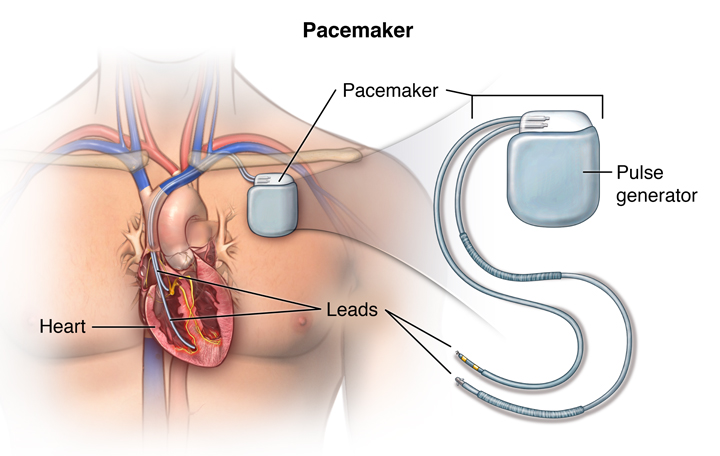

Overview

Package includes:

Days in hospital : 4 Days (For patient and one attendant)

Days in hotel : 10 Days (For patient and one attendant)

Room type in hospital : Shared

Room type in hotel : Private

Hotel category: Standard

Value added benefits of the Pacemaker Procedure Biventricular:

Ø Doctor consultation charges

Ø Lab tests and diagnostic charges

Ø Room charges inside hospital during the procedure

Ø Surgeon Fee

Ø Nursing charges

Ø Hospital surgery suite charges

Ø Anesthesia charges

Ø Routine medicines and routine consumables (bandages, dressings etc.)

Ø Food and Beverages inside hospital stay for patient and one attendant.

Extra benefits:

ü Interpreter

ü Visa assistance

Ø Site tourism of the city

Ø Follow up with the doctor

Ø Airport pick up and drop

Ø Free online consultation with the doctor

Ø Priority appointments with the doctor

Ø Room upgrade from sharing to private

Overview

Package includes:

Days in hospital : 1 to 2 Days (For patient and one attendant)

Days in hotel : 5 Days (For patient and one attendant)

Room type in hospital : Shared

Room type in hotel : Private

Hotel category: Standard

Value added benefits of the Pacemaker Procedure Double Chamber:

Ø Doctor consultation charges

Ø Lab tests and diagnostic charges

Ø Room charges inside hospital during the procedure

Ø Surgeon Fee

Ø Nursing charges

Ø Hospital surgery suite charges

Ø Anesthesia charges

Ø Routine medicines and routine consumables (bandages, dressings etc.)

Ø Food and Beverages inside hospital stay for patient and one attendant.

Extra benefits:

ü Interpreter

ü Visa assistance

Ø Site tourism of the city

Ø Follow up with the doctor

Ø Airport pick up and drop

Ø Free online consultation with the doctor

Ø Priority appointments with the doctor

Ø Room upgrade from sharing to private

Overview

Package includes:

Days in hospital : 3 to 4 Days (For patient and one attendant)

Days in hotel : 8 Days (For patient and one attendant)

Room type in hospital : Shared

Room type in hotel : Private

Hotel category: Standard

Value added benefits of the Permanent Pacemaker Implantation:

Ø Doctor consultation charges

Ø Lab tests and diagnostic charges

Ø Room charges inside hospital during the procedure

Ø Surgeon Fee

Ø Nursing charges

Ø Hospital surgery suite charges

Ø Anesthesia charges

Ø Routine medicines and routine consumables (bandages, dressings etc.)

Ø Food and Beverages inside hospital stay for patient and one attendant.

Extra benefits:

ü Interpreter

ü Visa assistance

Ø Site tourism of the city

Ø Follow up with the doctor

Ø Airport pick up and drop

Ø Free online consultation with the doctor

Ø Priority appointments with the doctor

Ø Room upgrade from sharing to private